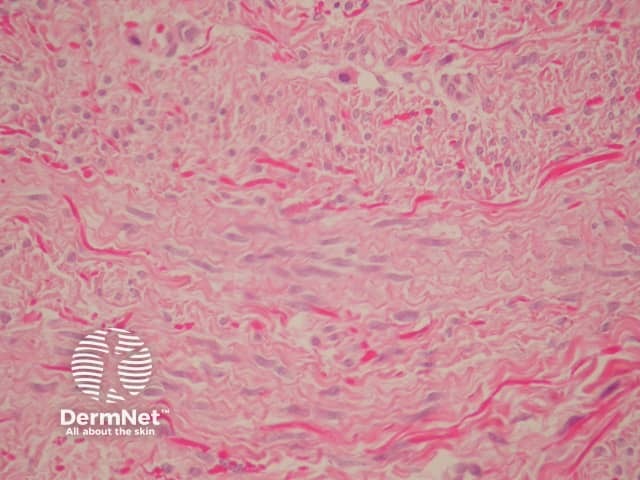

Sections show a subtle, ill-defined, plaque-like dermal proliferation (figure 1). The cells are uniform, slender, spindle-shaped and bland. The cells contain evenly distributed chromatin or vesicular with small nucleoli and indentations is in keeping with a myofibroblastic line of differentiation. Characteristically, the cells are arranged parallel to the epidermis (figures 2, 3).

Immunohistochemically, neoplastic cells may express some actin and CD34 positivity. Elastic fibres are increased which can be demonstrated with elastic stains.